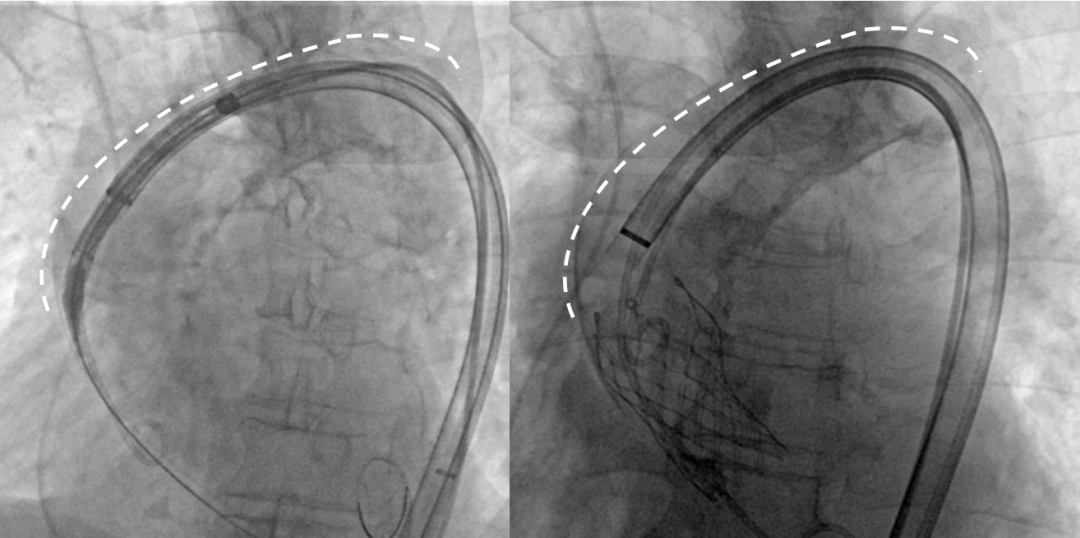

Step 4.输送系统进入:过弓性能优异,悬空通过,整体过程未将鞘管顶起至弓顶部

Step 5.瓣膜定位与释放:高起始位逐渐向下推送保持良好同轴性,无位移

Step 6.工作位观察:真实瓣环下方2mm,位置合适,决定释放,一次完成

Step 7.瓣膜脱钩:脱钩稳定无位移

Step 8.最终造影:真实瓣环下方3mm标准位,完全同轴,轻微反流,猪尾撤出后反流完全消失

Step 10.验证器械同轴性,完全同轴